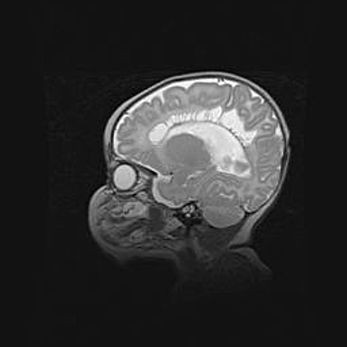

Церебральная ишемия II.

Возраст: 5 дней

Вес: 3400 г

Пол: женский

Окружность головы: 35 см

Срок гестации: 39 недель

Церебральная ишемия – это заболевание, характеризующееся недостаточностью (гипоксией) либо полным прекращением (аноксией) снабжения мозга кислородом по причине закупорки одного или нескольких сосудов. Это приводит к  что метаболическим расстройствам различной степени тяжести в тканях головного мозга, развитию коагуляционных некрозов и гибели нейронов.